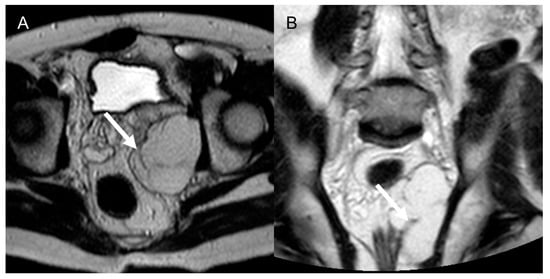

In myxofibrosarcoma and myxoid LPS, the water-like sign on T2-w sequences is related to high myxoid matrix content (≥75%) and has been associated with an increased risk of local recurrence and worse prognosis [48], as it is associated with shorter metastasis-free survival [27]. A higher amount (≥50%) of fatty content also seemed to correlate with higher grade and shorter metastasis-free survival [27] (Figure 10).

Figure 10.

Dedifferentiated retroperitoneal liposarcoma in a 50-year-old man. Axial (A) and coronal (B) T2-weighted MR images show an 8 cm fatty mass in the felt pelvis, with internal septa (arrows). The lesion was histologically confirmed after surgical excision.